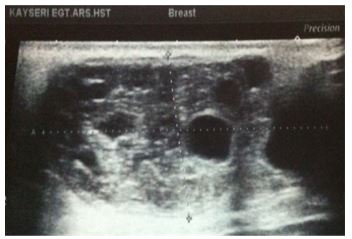

Alamer et al. [13] reported a 66-year-old lady who was known to have hypertension and diabetes mellitus who had presented with a palpable mass within her left breast that was associated with pain over a period of a long time. She did not have any nipple discharge or fever. She also did not have any history of breast trauma, hormone replacement therapy, or a family history of carcinoma of the breast. Her clinical examination showed a large palpable mass which was identified within her left breast with regular borders. Her nipple, areolar, and skin were normal. There was no evidence of palpable lymph node enlargement in her left axilla. Her general examination, systemic examinations and examination of her right breast and right axilla were normal. The results of her investigations including haematology blood tests, biochemistry blood tests, and chest x-ray were normal except elevated serum glucose result. She had a mammogram which showed a large oval and dense mass in the upper outer quadrant of her left breast (see figures 11 and 12). The mass was noted to be lobulated and well-circumscribed in its contours and to have measured 9.2 cm x 7.5 cm. No microcalcification was noted. The nipple, areolar, and skin were normal. The axillary lymph nodes were normal and the right breast was normal. Based upon the mammography examination features of the lump an impression of an usual large dense mass within her left breast was made and coded as BIRAD4A, taking into consideration the age of the patient, and further assessment with ultrasound scan was recommended. The differential diagnoses that were considered included: Phyllodes tumour, pseudo-angiomatous stromal hyperplasia (PASH), and well circumscribed carcinoma of the breast.

She had ultrasound scan of the breast which showed a large heterogeneous and lobulated mass within the upper quadrant of her left breast which had corresponded to the mammographic features. Few internal anechoic cysts were visualized within the peripheral aspects of the breast lesion. Doppler interrogated images did not show any internal vascularity within the mass (see figures 13, 14, and 15). There were no enlarged associated axillary lymph nodes found. She had ultrasound scan-guided biopsy from the lesion. She did have computed tomography (CT) scan for further assessment of the breast lump which did reveal a large hypo-dense mass within her left breast. It also revealed very tiny and thin internal septations were visualized. There was no peripheral enhancement and no internal enhancement. The mass did measure 6.8 cm x 6.2 cm x 9 cm in maximum dimensions (see figures 16 and 17). No axillary lymph nodes were found. The rest of the intra-thoracic and abdominal structures were found to be normal. Pathology examination of the biopsy specimen showed scanty material which had consisted of fragmented eosinophilic membranes that had laminated appearance in keeping with the diagnosis of hydatid cyst. A final diagnosis of hydatid cyst of the breast was made. The patient was referred to the surgeons for surgical excision of the hydatid cyst of the breast at the time of the report of the article. The lesson that needs to be learnt from this case report is the fact that diagnosis of hydatid cyst can be established pre-operatively with careful history taking, clinical examination radiology imaging including ultrasound scan, CT scan, and ultrasound scan-guided biopsy for histopathology/cytology examination which would guide the surgeon to undertake a careful complete surgical excision of the without spillage of the contents of the hydatid cyst.